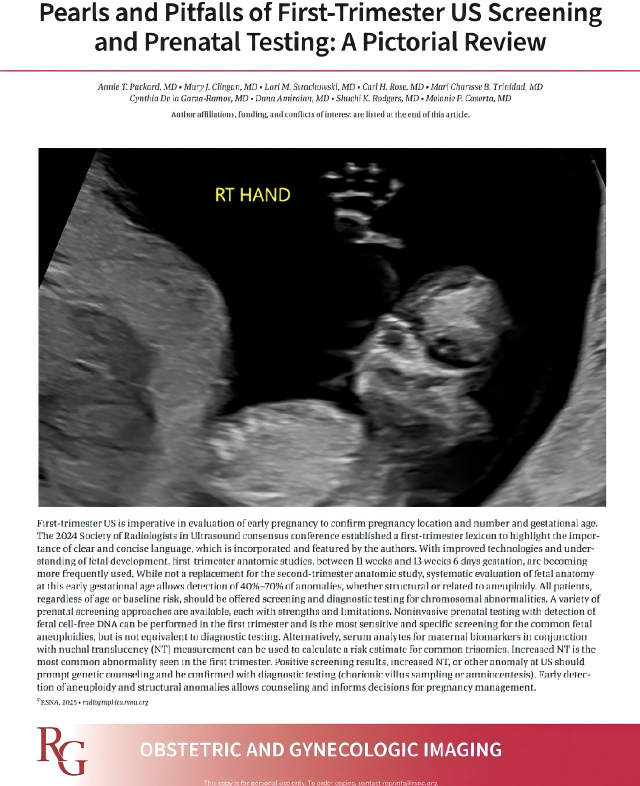

(3) 2025 Article in Radiographics

In 2025, the Radiological Society of North America (RSNA) published an article titled "Key Points and Pitfalls in First-Trimester Ultrasonographic Screening and Prenatal Examinations: An Imaging Review" in the journal Radiographics:

The article points out: Ultrasonography in the first trimester is essential for evaluating early pregnancy, aiming to determine the location, number, and gestational age of the pregnancy. With technological advancements and deeper understanding of fetal development, anatomical assessment in the first trimester (from 11 weeks to 13 weeks and 6 days) is becoming increasingly common. Although it cannot replace second-trimester anatomical assessment, systematic evaluation of fetal anatomy at this earlier gestational age can detect 40% to 70% of abnormalities, both structural and those associated with chromosomal aneuploidy. An important part of this assessment also includes examination of the umbilical cord.